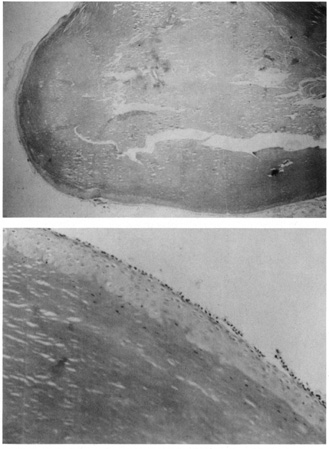

The ichthyoses are a group of inherited disorders of keratinization characterized by dryness and excessive scaling of the skin. Ichthyosis vulgaris (autosomal dominant) often demonstrates fine scaling of the lids, lashes, and surrounding skin; X-linked ichthyosis, additionally, may show large, darker, polygonal scales. One of the two rare autosomal recessive types, lamellar ichthyosis, demonstrates large, thick scales often with ectropion of the lids and conjunctival changes. In ichthyosis vulgaris, there is compact orthokeratosis overlying a markedly diminished or absent granular layer without significant inflammation in the dermis (Fig. 16). X-linked and autosomal recessive ichthyoses also show compact orthokeratosis, but the changes in the granular layer are not distinctive. In autosomal dominantly inherited epidermolytic hyperkeratosis, a distinct histologic change is characterized by intracellular edema, vacuolization of keratinocytes, and the appearance of large, clumped keratohyalin granules, especially in the superficial portions of the epidermis.

Fig. 16. A. Ichthyosis vulgaris showing compact orthokeratosis with a markedly diminished granular layer. B. Epidermolysis bullosa, recessive dystrophic type, with a noninflammatory subepidermal bulla.